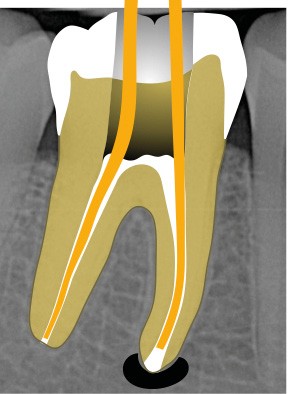

13. si possible, mise en place d’un champ opératoire sur la dent concernée, de sorte à isoler la zone de perforation de toute humidité (fig. 2) ;